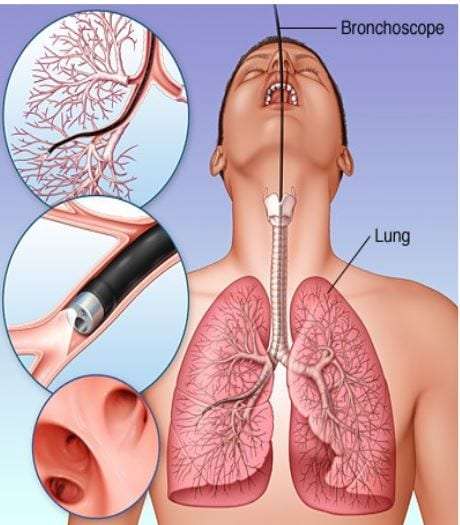

Роль легких в метаболических процессах